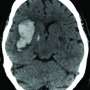

![]() | Standard blood pressure target is sufficient for treating some strokesAn international stroke study found that standard and intensive blood pressure treatments were equally effective in the emergency treatment of acute intracerebral hemorrhage, a type of stroke caused by bleeding into the brain. Patients whose systolic blood pressure was reduced rapidly in emergency rooms to standard levels used to treat acute stroke (140-179 mm Hg) did as well as patients whose pressure was reduced to intensive levels (110-139 mm Hg). The study, published in the New England Journal of Medicine, was funded by the NIH's National Institute of Neurological Disorders and Stroke (NINDS). |